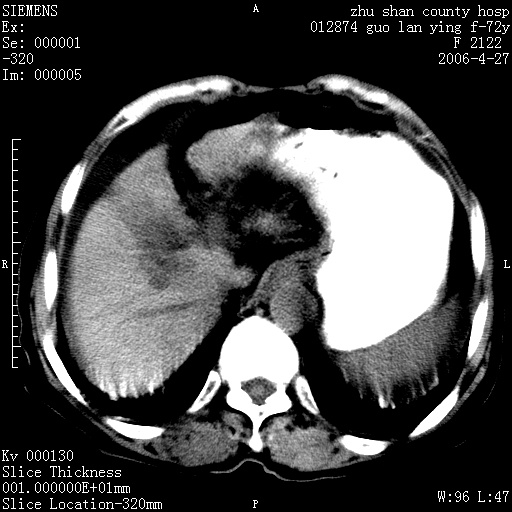

病人 女性 72岁 b超要求ct检查!

平扫所见:胆囊区两点壮高密度影,灶周有伪影{请问楼主患者有手术病史?}。肝实质内未见明显异常{建议强化或mri}.腹腔有少量积液,脾明显增大.右肾形态似不规则?

肝脏缩小,脾脏增大,肝脾外缘及胆囊窝液性密度影,肝脾ct值正常,胆囊区见两个类圆形高密度影,下腔静脉前方类圆形软组织密度影为肝脏岛叶,胃幽门区见软组织密度影,十二指肠钡剂充盈不好.

1:腹水2:胆囊结石3肝硬化?(不确定,请结合临床)4幽门区占位?(建议胃肠透视)

肝硬化,脾大,少量腹水

肝硬化、腹水、脾大,胆囊结石可以肯定。只是肝右叶两个低密度有必要增强确定一下;排除小肝癌。

谢谢牟教授在百忙之中还认真的点评我的帖子!也谢谢大家的鼎力相助,此病人是我们医院护理部主任的母亲!病人以前无特别不舒适!昨天b超后发现有问题!做ct的目的在于排除肝内占位性病变,此病人以前无手术外伤史.